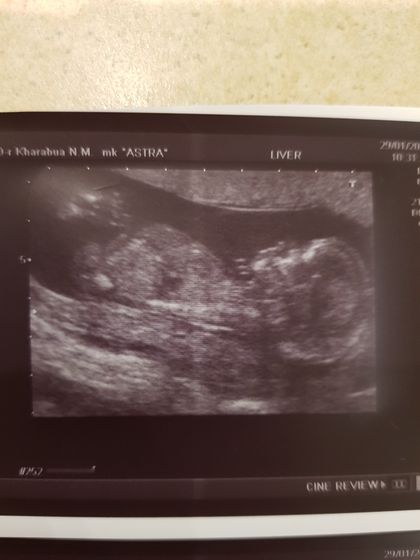

Была на первом скрининге. 14 неделек. Узист сказала пол, мне интересно, кто опытный, видно по фото какой именно пол? Я пересмотрела кучу фото и постов, ну никак не вижу ?

По такому фото вам и узист не скажет. Там есть определённые параметры, развития половых органов по которым они говорят. Мне на 1м скрининге сказали верно.

По такому фото не Сказать